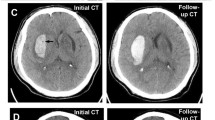

Moderation Effect of ICH Volume

Furthermore, we found a significant positive moderation by ICH volume on the reduction of 30-day mortality following surgical treatment (OR: 0.905; 95% CI: 0.902–0.908; p < 0.01). To distinguish between patients with low and high volumes, we established cut-off point for volume moderation at 29.47 ml (p < 0.01). Among patients above that threshold (49.19%), surgical treatment was associated with lower risk of 30-day mortality (OR: 0.037; 95% CI: 0.001–0.414; p = 0.03), a higher GCS score upon admission (OR: 0.764; 95% CI: 0.657–0.872; p < 0.01) and a higher entropy (OR: 0.994; 95% CI: 0.986–0.998; p = 0.04). A higher glucose level upon admission (OR: 1.22; 95% CI: 1.063–1.443; p < 0.01), presence of IVH (OR: 3.979; 95% CI: 1.495–11.401; p < 0.01) and a higher fractal dimension (OR: 1.489; 95% CI: 1.114–2.091; p = 0.01) were independently associated with a higher risk of 30-day mortality among those patients. In terms of patients with lower ICH volume (50.81%) higher GCS score (OR: 0.570; 9%% CI: 0.435–0.695; p < 0.01) and subtentorial location (OR: 0.035; 95% CI: 0.001–0.442; p = 0.02) were independently associated with lower risk of 30-day mortality and higher energy was associated with higher risk of 30-day mortality (OR: 1.419; 95% CI: 1.175–2.302; p = 0.03) (Table 4, Fig. 4).

Our research also identified a significant moderating role of volume in the connection between 30-day mortality and surgical intervention. Following an ICH removal, a significant reduction in 30-day mortality was observed only in patients with larger ICH volumes. As previously documented in the literature, ICH size is one of the most important predictors of outcome [17]. Larger ICHs are associated with a mass effect, potentially leading to brain herniation. Additionally, a greater volume of blood can amplify its toxic impact on brain tissue [18] and is linked to an increased risk of ICH growth and early deterioration [19]. Our findings are consistent with other researchers who have also proposed that larger ICHs are an indication for surgical intervention [4, 5]. Other research groups also found that patients with such ICHs are more frequently candidates for surgery [20]. In contrast to ICH energy, common risk factors had similar impacts on mortality both in groups with larger and smaller ICH.